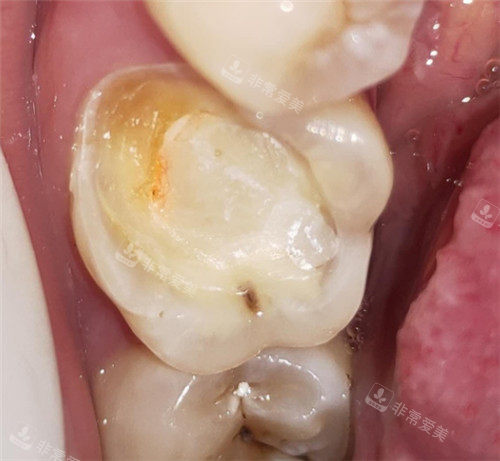

牙根龋坏模型图片

牙齿龋坏清理图

牙齿龋坏展示图